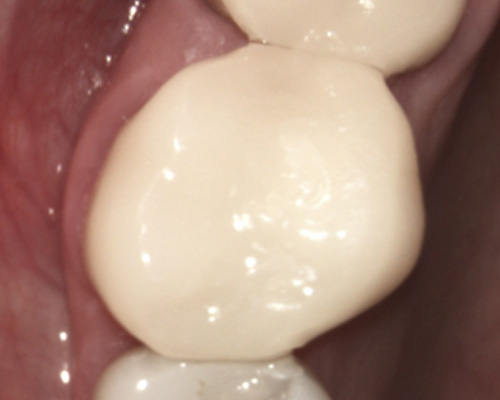

Decayed and Cracked Tooth.

Before Broken Tooth

After One-Visit CEREC Crown Technology

Decayed and Cracked Tooth.

Before Broken Tooth

After One-Visit CEREC Crown Technology